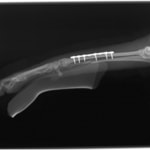

トイプードル 右遠位橈尺骨短斜骨折のALPSによる内固定

Locking Compression Plate

LCPは、スクリュー(ネジ)とプレート(金属の板)をロックする特殊な構造により骨折部位を固定する新しい世代のプレートシステムです。ひとつのホールでロッキングスクリューとスタンダードスクリューの使用を選択できるユニークな構造をしているため、骨折断端間の圧迫を目的とした従来型プレート固定法に加え、高い角度安定性を有するロッキングスクリューを用いた固定法の選択が可能です。従来のプレートシステムでは困難だった部分の骨折や癒合不全の症例に高い治療効果をもたらします。